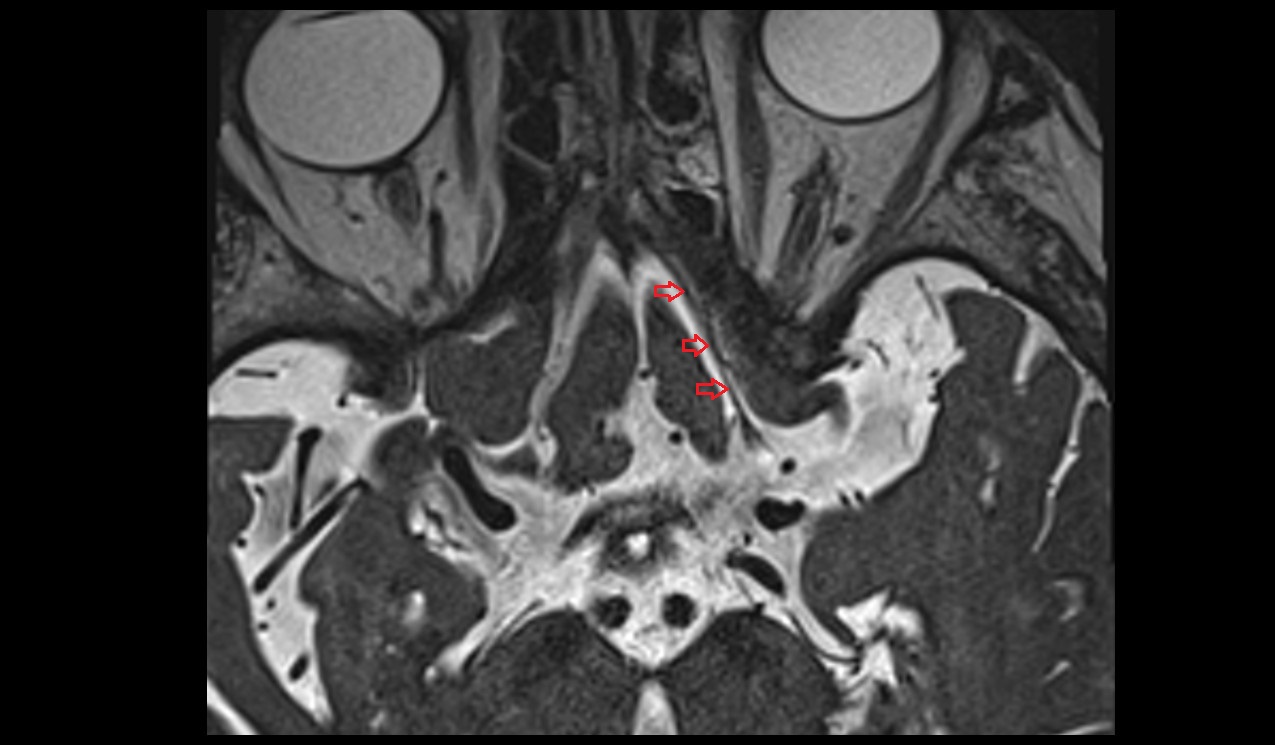

- Peripheral zone of prostate

- Anterior Fibromuscular Stroma of prostate

- Central zone of prostate

- Transitional zone of prostate